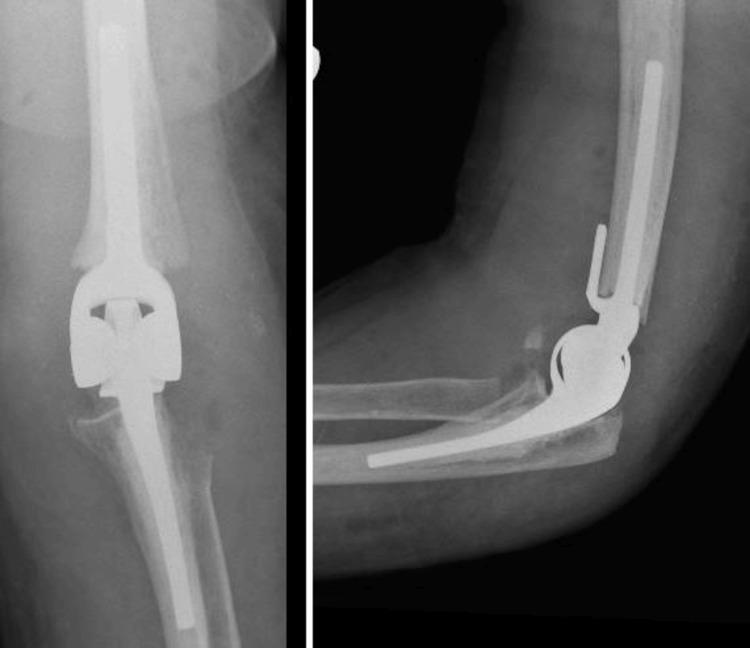

Introduction Complex distal humerus fractures pose significant challenges in orthopedic surgery, especially when traditional open reduction and internal fixation (ORIF) is not feasible. Primary elbow arthroplasty has emerged as an alternative treatment option for these fractures, but its application remains limited. This study aimed to evaluate the functional outcomes, patient selection criteria, and follow-up results of primary elbow arthroplasty in the management of complex distal humerus fractures. Methods A retrospective review was conducted on 15 patients who underwent primary elbow arthroplasty for Orthopaedic Trauma Association (OTA) type C distal humerus fractures between 2017 and 2023 at our institution. Inclusion criteria were patients aged 18 years or older who were offered either total elbow or hemiarthroplasty for acute complex distal humerus fracture. Data were collected from patient medical records, including demographic information, fracture classification, surgical details, and postoperative follow-up. Functional outcomes were assessed using the Oxford Elbow Score (OES) and Mayo Elbow Performance Score (MEPS). Complications were documented, and descriptive statistics were used to summarise the findings. Results The mean age of the patients was 71.8 years (IQR 17 years), with 12 females and three males. The mean time to surgery was 14.7 days post-injury (IQR: 12 days). The mean follow-up duration was 52 weeks (range: 8-234 weeks, IQR: 27 weeks) and variability was noted. The mean flexion-extension arc at the final follow-up was 93° (IQR: 32.5°). The mean OES was 46 (IQR: 22), and the mean MEPS was 75 (IQR: 37), indicating good to excellent functional outcomes. Scores for two patients were not available due to dementia. Reported complications included one case of ulnar sensory symptoms and one case requiring metalwork removal following olecranon osteotomy. Conclusion Primary elbow arthroplasty provides a viable treatment option for complex distal humerus fractures, demonstrating significant functional improvements and high patient satisfaction. However, the variability in follow-up and subjective decision-making underscores the need for standardized protocols. Future multicenter, prospective studies with larger cohorts and standardized follow-up protocols are recommended to confirm these findings and optimize patient care.

https://cdn.ncbi.nlm.nih.gov/pmc/blobs/2d74/11364086/65e05f423847/cureus-0016-00000065851-i01.jpg